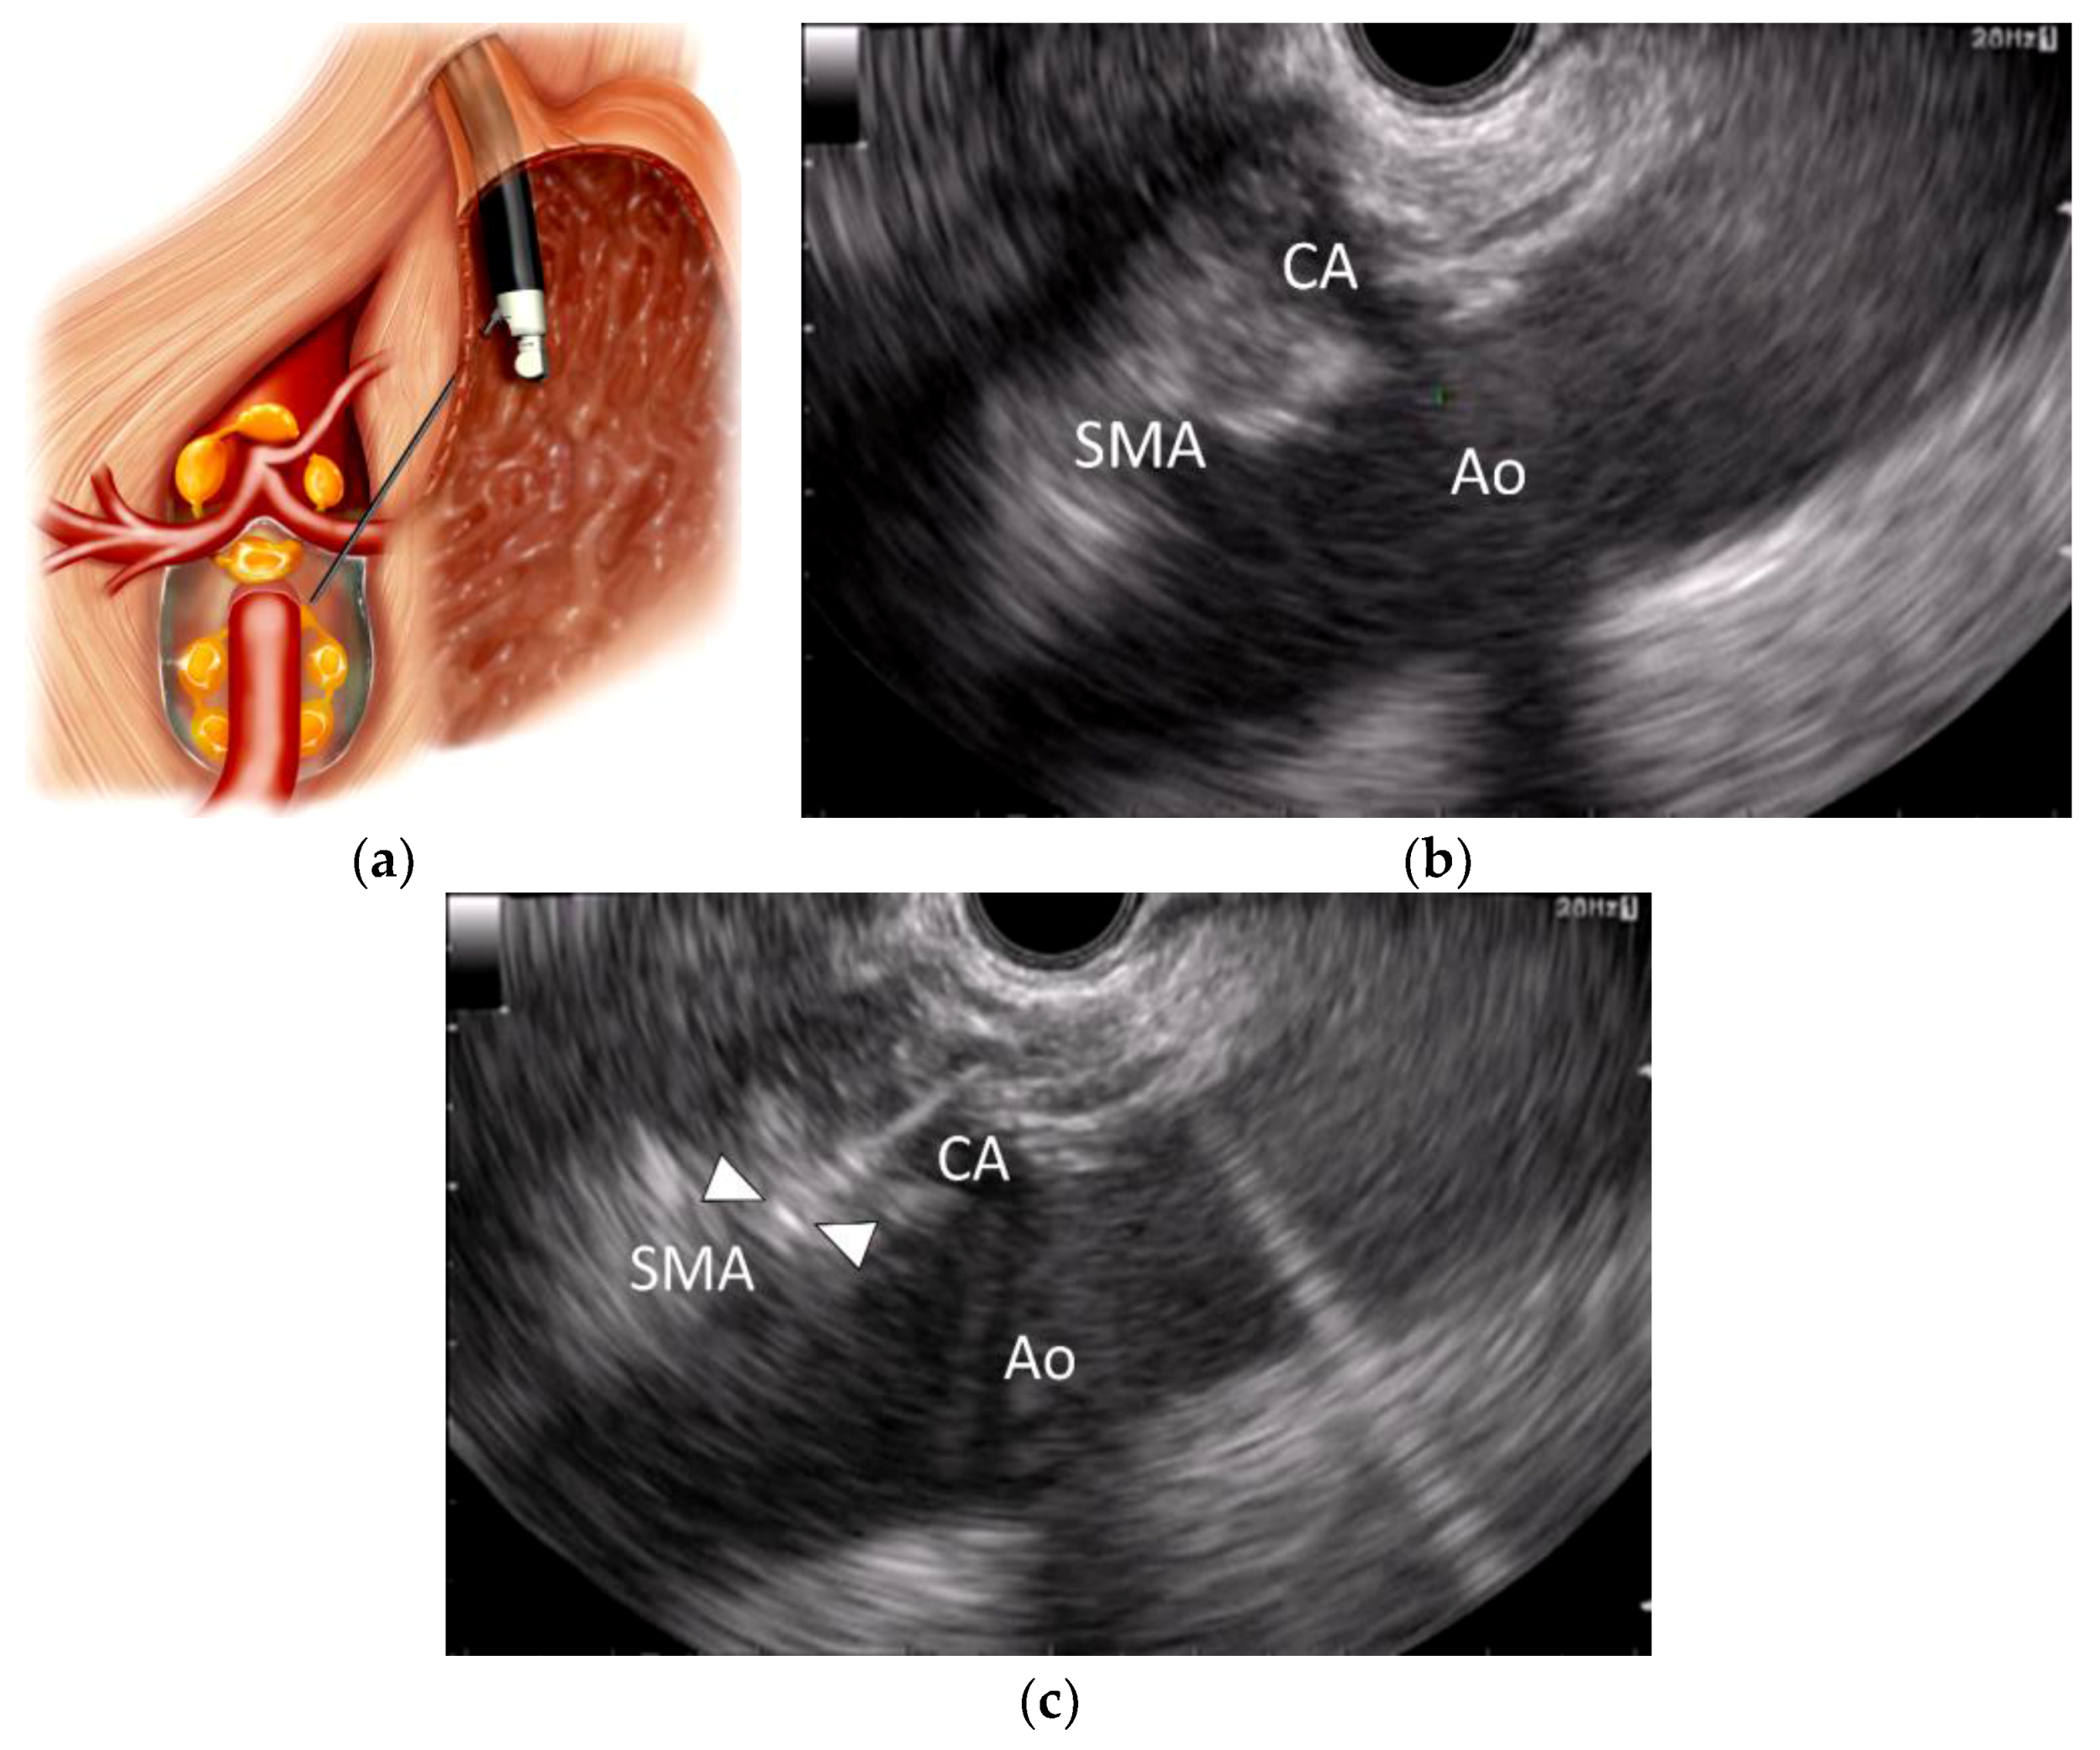

The celiac trunk is the first anterior branch of the abdominal aorta, which supplies the foregut structures.